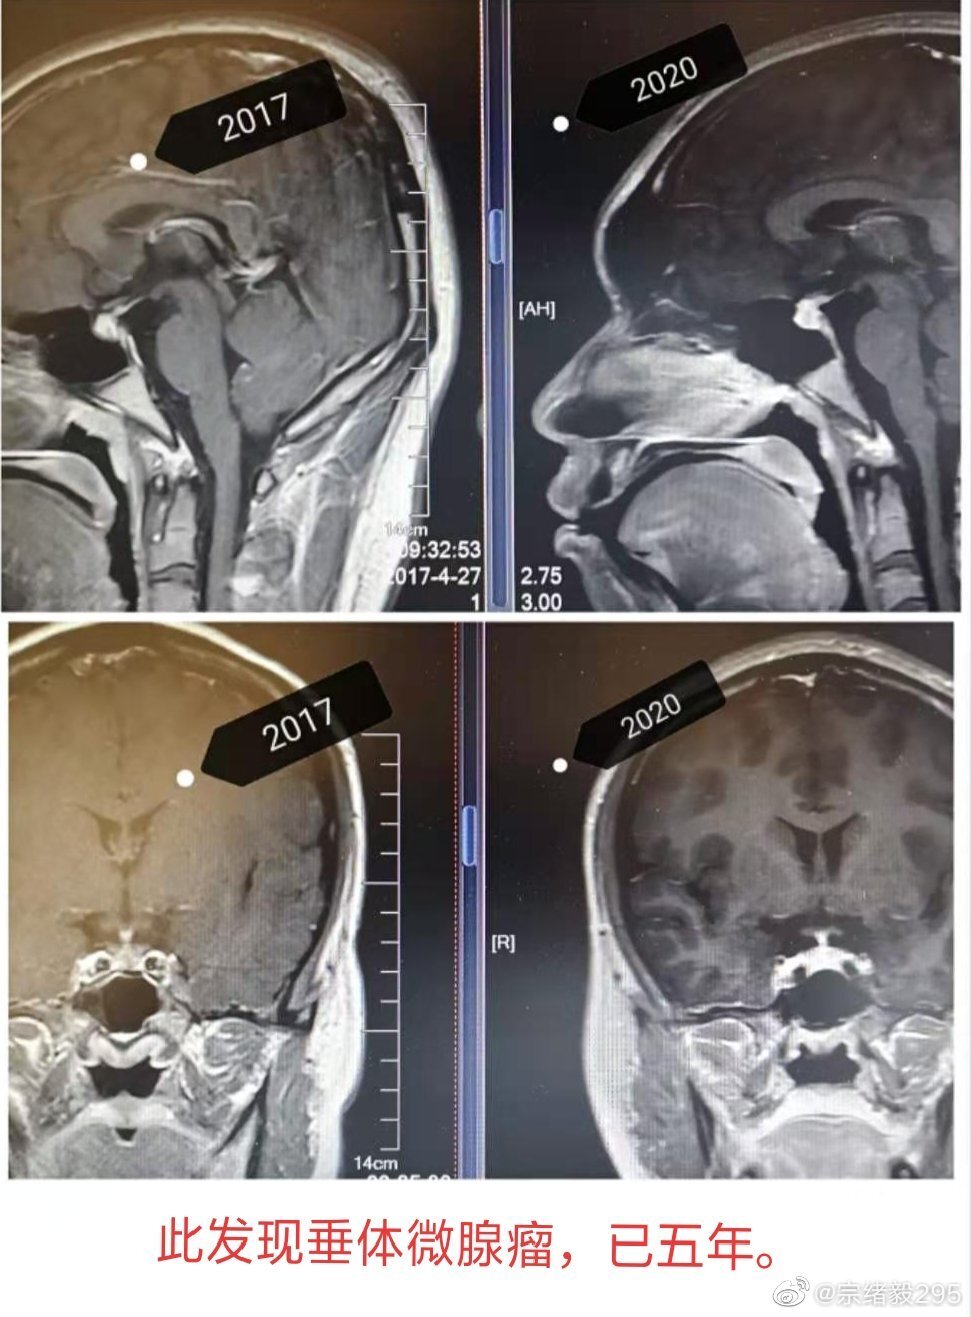

200366 垂体瘤 两次比较

图片尺寸1012x1032